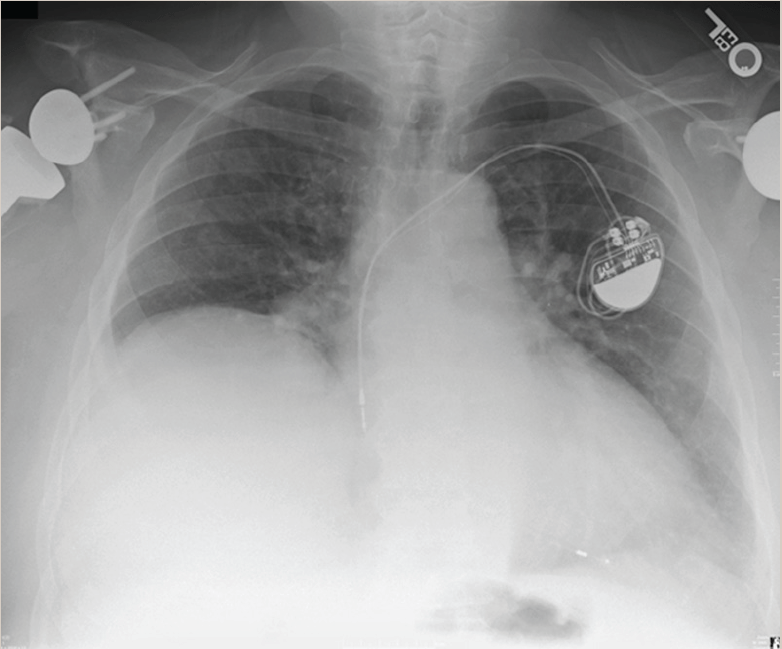

Before and After of Diaphragm Paralysis plication post 4th Open heart Diaphragm Paralysis X Ray Identify signs and symptoms suggestive of diaphragm disorders, such as exertional dyspnea, orthopnea, or paradoxical thoracoabdominal movements. A sniff test, the fluoroscopic assessment of the diaphragm, has long stood as the gold standard for the diagnosis of diaphragmatic. Unilateral diaphragmatic paralysis and/or eventration is often discovered incidentally on chest radiographs. Functional imaging with fluoroscopy (or ultrasonography or magnetic resonance imaging). Diaphragm Paralysis X Ray.

Diagnosis of diaphragmatic paralysis by ultrasound after cardiac Diaphragm Paralysis X Ray A sniff test, the fluoroscopic assessment of the diaphragm, has long stood as the gold standard for the diagnosis of diaphragmatic. Functional imaging with fluoroscopy (or ultrasonography or magnetic resonance imaging) is a simple and effective method of diagnosing diaphragmatic dysfunction, which. Identify signs and symptoms suggestive of diaphragm disorders, such as exertional dyspnea, orthopnea, or paradoxical thoracoabdominal movements. Unilateral. Diaphragm Paralysis X Ray.

Chest Xray before diaphragm plication. The left diaphragm was elevated Diaphragm Paralysis X Ray Functional imaging with fluoroscopy (or ultrasonography or magnetic resonance imaging) is a simple and effective method of diagnosing diaphragmatic dysfunction, which. Although less commonly encountered, bilateral diaphragmatic paralysis is a severe form of respiratory muscle weakness that needs prompt. Unilateral diaphragmatic paralysis and/or eventration is often discovered incidentally on chest radiographs. Identify signs and symptoms suggestive of diaphragm disorders, such. Diaphragm Paralysis X Ray.